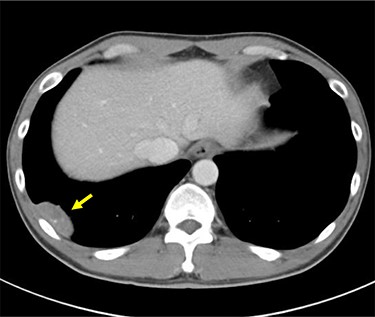

An abnormal shadow was detected on the chest radiograph of a 44-year-old man with a history of pulmonary tuberculosis, who underwent a whole-body chemotherapy regimen of rifampicin, isoniazid, ethambutol and pyrazinamide at age 42. He was a former smoker with 10 pack-years. Physical examination and routine laboratory tests did not reveal any abnormalities. Both chest radiographs during chemotherapy and completion of treatment showed consolidation in the right upper field and a 44 mm nodule in the right lower lung field with no interval change. Enhanced computed tomography (CT) revealed a well-defined elliptical nodule (44 × 20 mm) located in the right posterior thoracic cavity (Fig. 1). A CT scan also demonstrated bilateral consolidation in the upper lobe. Pleural tuberculoma, solitary fibrous tumor or malignant tumor was suspected, and thoracoscopic resection of the chest wall tumor was performed. Intraoperatively, a nodule was found between the visceral pleura and parietal pleura, although loose adhesion was observed throughout the entire thoracic cavity (Fig. 2). There was no disseminated disease in the thoracic cavity. It was determined to be noninvasive, and en bloc resection was performed. Pathological findings showed capsuled chronic granulomatous inflammation with Langhans giant cells and caseous necrosis (Fig. 3a). Ziehl–Neelsen staining revealed a red bacillus, resulting in pleural tuberculoma diagnosis (Fig. 3b). Smears for acid-fast bacilli and PCR for tuberculosis were positive. However, an acid-fast bacterial culture was negative within 6 weeks, and the patient’s recovery was uneventful after a 2-month follow-up period without chemotherapy.

Preoperative enhanced CT scan demonstrates a well-defined 44 mm solid nodule with calcification in the right lateral thoracic cavity (yellow arrow). CT: computed tomography.